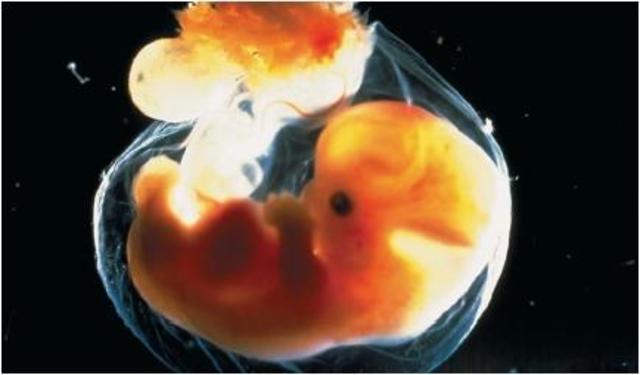

• embryonic stage

embryonic stage

the embryonic stage is where the fetus is becoming a baby and growing at a rapid speed. this goes until the fourth week until the eight week.

• body system

body system

This is where the fetus divides into three layers each will become an important body system. About 22 days after the conception the neural tube forms. this tube will later form into the central nervous system, the spinal cord and the brain. this domain is physical

• physical development

physical development

This is where the physical appearance of the fetus begins to form. the head begins to form quickly followed by the eyes, nose, ears, and mouth.The cardiovascular system is where the activity begins as the blood vessel that will become the heart start to pulse.buds that will form the arms and legs will appear. this domain is physical